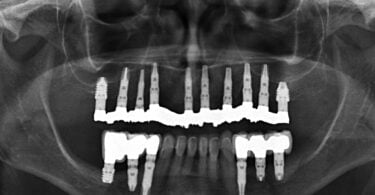

Quatro dos seis implantes foram de 5,5 mm de comprimento por 5 mm de diâmetro, um implante foi de 6,5 mm de comprimento por 3,75 mm de diâmetro e o último implante foi de 6,5 mm de comprimento por 5 mm de diâmetro (figura 2).

As seguintes imagens apresentam um dos casos incluídos no estudo (figura 03 – 15).